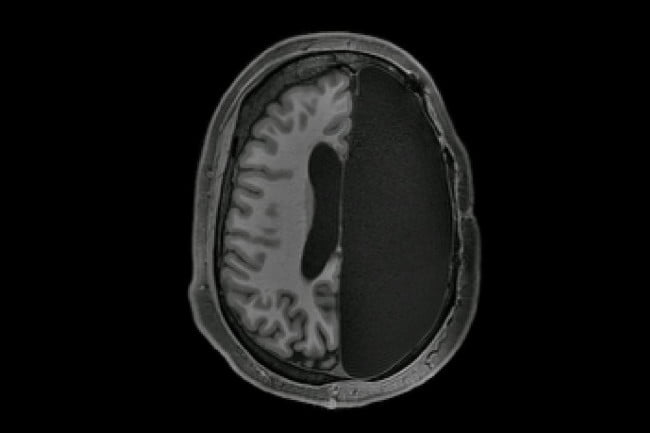

Você consegue sobreviver com metade do seu cérebro removido?

Um novo estudo revelou a notável capacidade do cérebro humano de se…